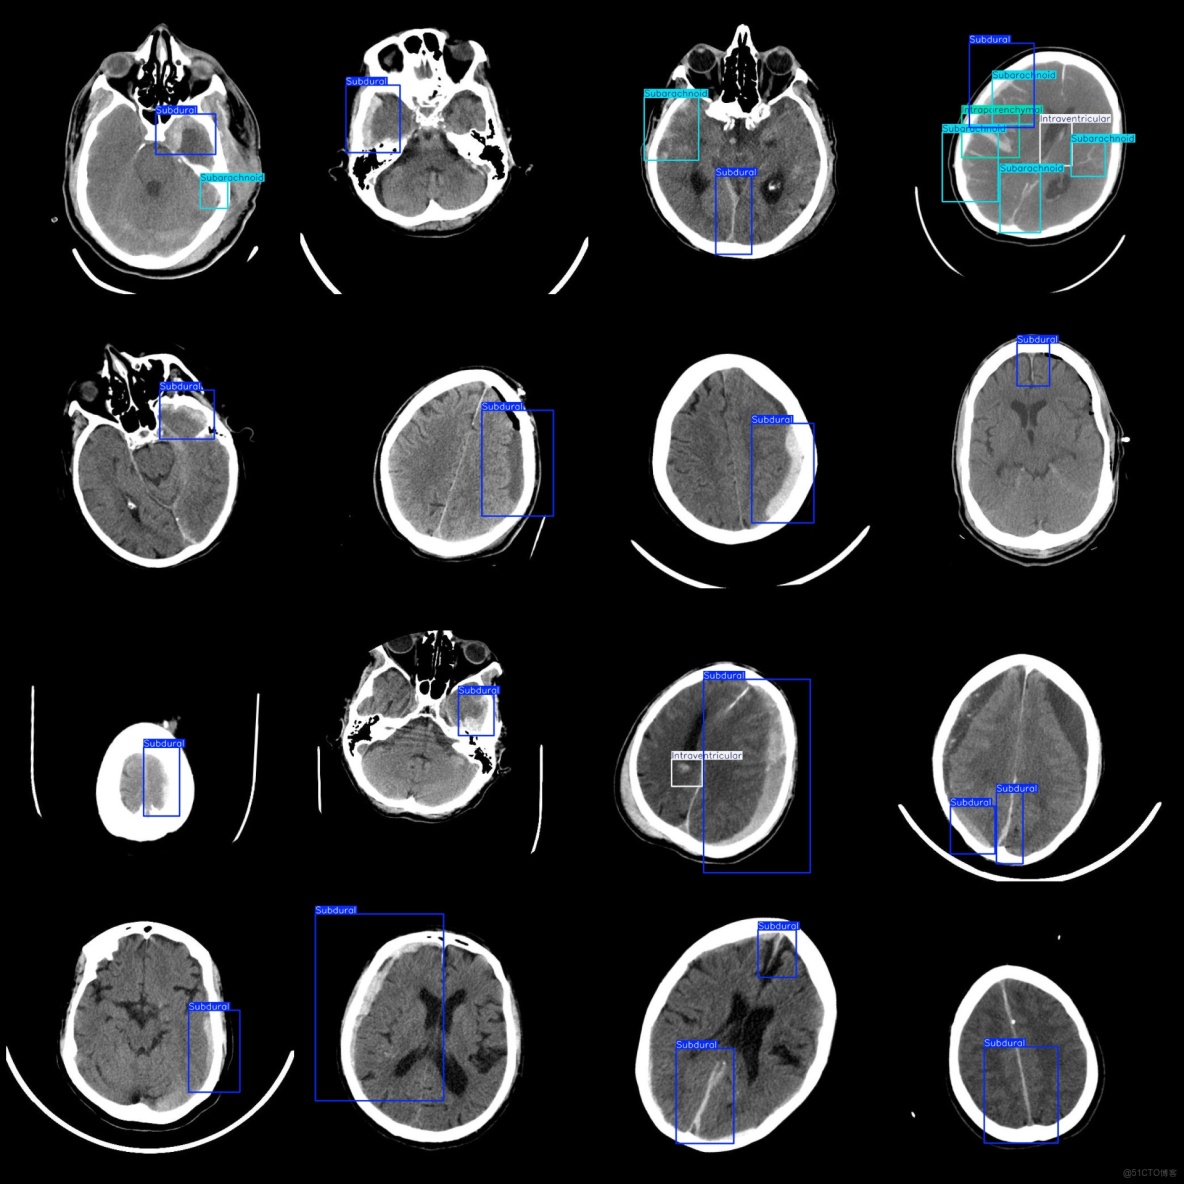

標註類別名稱(注意yolo格式類別順序不和這個對應,而以labels文件夾classes.txt為準):["Intraparenchymal","Intraventricular","Subarachnoid","Subdural"]

每個類別標註的框數:

Intraparenchymal (腦實質內出血) 框數 = 655

Intraventricular (腦室內出血) 框數 = 141

Subarachnoid (蛛網膜下腔出血) 框數 = 579

Subdural (硬膜下出血) 框數 = 4156

總框數:5531

標註例子: